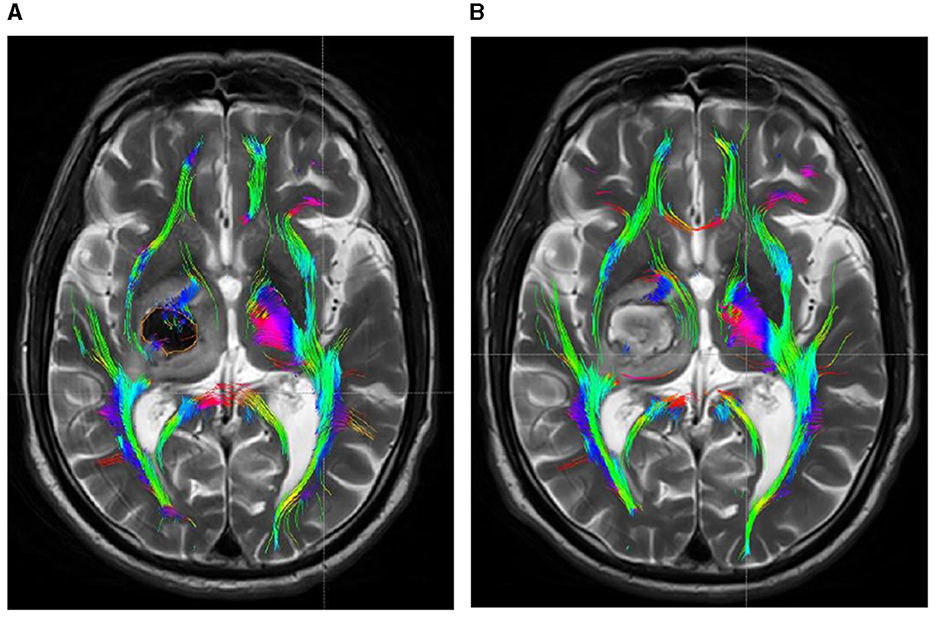

Figure 5

DTI picture of a patient with a minor basal ganglia hemorrhage, treated with conservative pharmacological treatment within 48 h of admission (A) and 1 month post-treatment (B). (A) A hematoma is present within the orange marker, causing deformation and elevation of the posterior limb of the internal capsule due to compression by the hematoma. The CST has thinned due to partial rupture. Upon complete absorption of the hematoma, the posterior limb of the internal capsule remains marginally compressed due to cerebral edema, resulting in medial displacement of the CST. The original rupture exhibits minimal repair connections; however, the CST remains quite small.